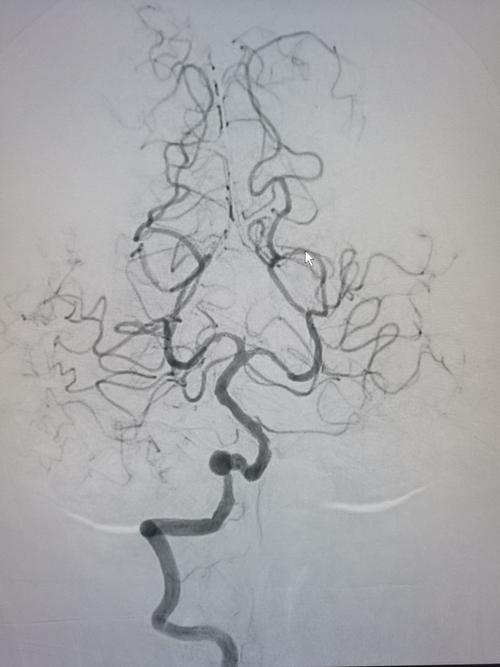

右椎动脉造影显示v4段动脉瘤,pica似乎未见.

行左侧椎动脉造影,见动脉迂曲,动脉瘤在小脑上动脉起始.